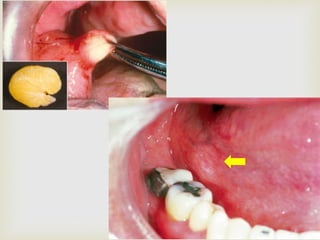

 Benign tumour of fat tissue

 First described by ROUX (in 1848) as yellow epulis

 Relatively rare intraoral tumour; more frequent in

subcutaneous tissues of the neck

 The cells of lipoma differ metabolically from the

normal fat cells even though they are histologically

similar

LIPOMA

 Usually found in adults above 40yrs

 No gender predilection

 Buccal mucosa and buccal vestibule are the most

common sites

 Can also occur on tongue, floor of the mouth and

gingiva

 Slow growing; soft, smooth- surfaced nodular mass

 Sessile or pedunculated

 Mostly less than 3cms in size

 INTRAORAL LIPOMAS can be classified into

 Superficial form

 Well encapsulated

 Yellow in colour

 Soft; freely movable beneath the mucosa

 Diffuse form

 Present in deeper surfaces; produces surface elevation

 More diffuse and gives the feel of a fluid on palpation